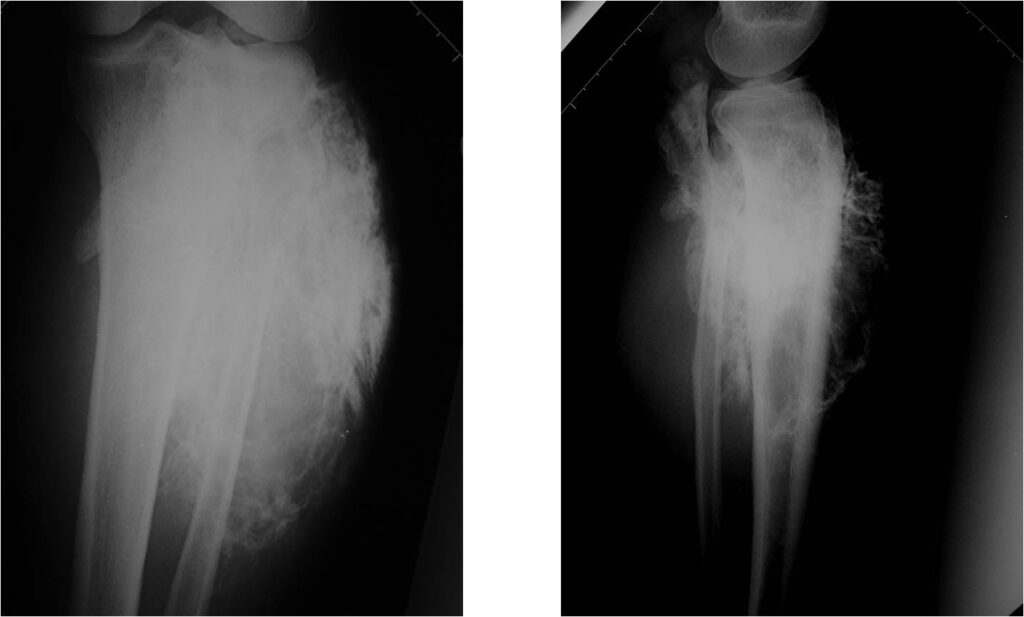

Radiographic Presentation: Conventional Osteosarcoma

There are 3 radiographic presentations for osteosarcomas, depending upon the amount of osteoid/ossification and calcium deposition:

- Mixed sclerotic and lytic, permeative lesion most common radiographic presentation

- Purely osteoblastic, permeative lesion: dense sclerosis and osteoid production

- Purely lytic, permeative lesion: little osteoid production and/or minimal calcium deposition in osteoid

Conventional osteosarcomas are permeative lesions on plain radiographs (borders of the lesion cannot be clearly delineated)

- Wide zone of transition from lytic/sclerotic areas of tumor to normal bone

- Makes borders of lesion hard to define

- Most (90%) arise from the metaphysis of the bone

- Rarely (10%) arise from the diaphysis

- Most conventional osteosarcomas (90-95%) extend through the bone into the soft tissues and form a soft tissue mass outside of the bone